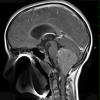

NEOPLASMS (NON-GLIAL NON-NEURONAL)

Choroid plexus papilloma (8)